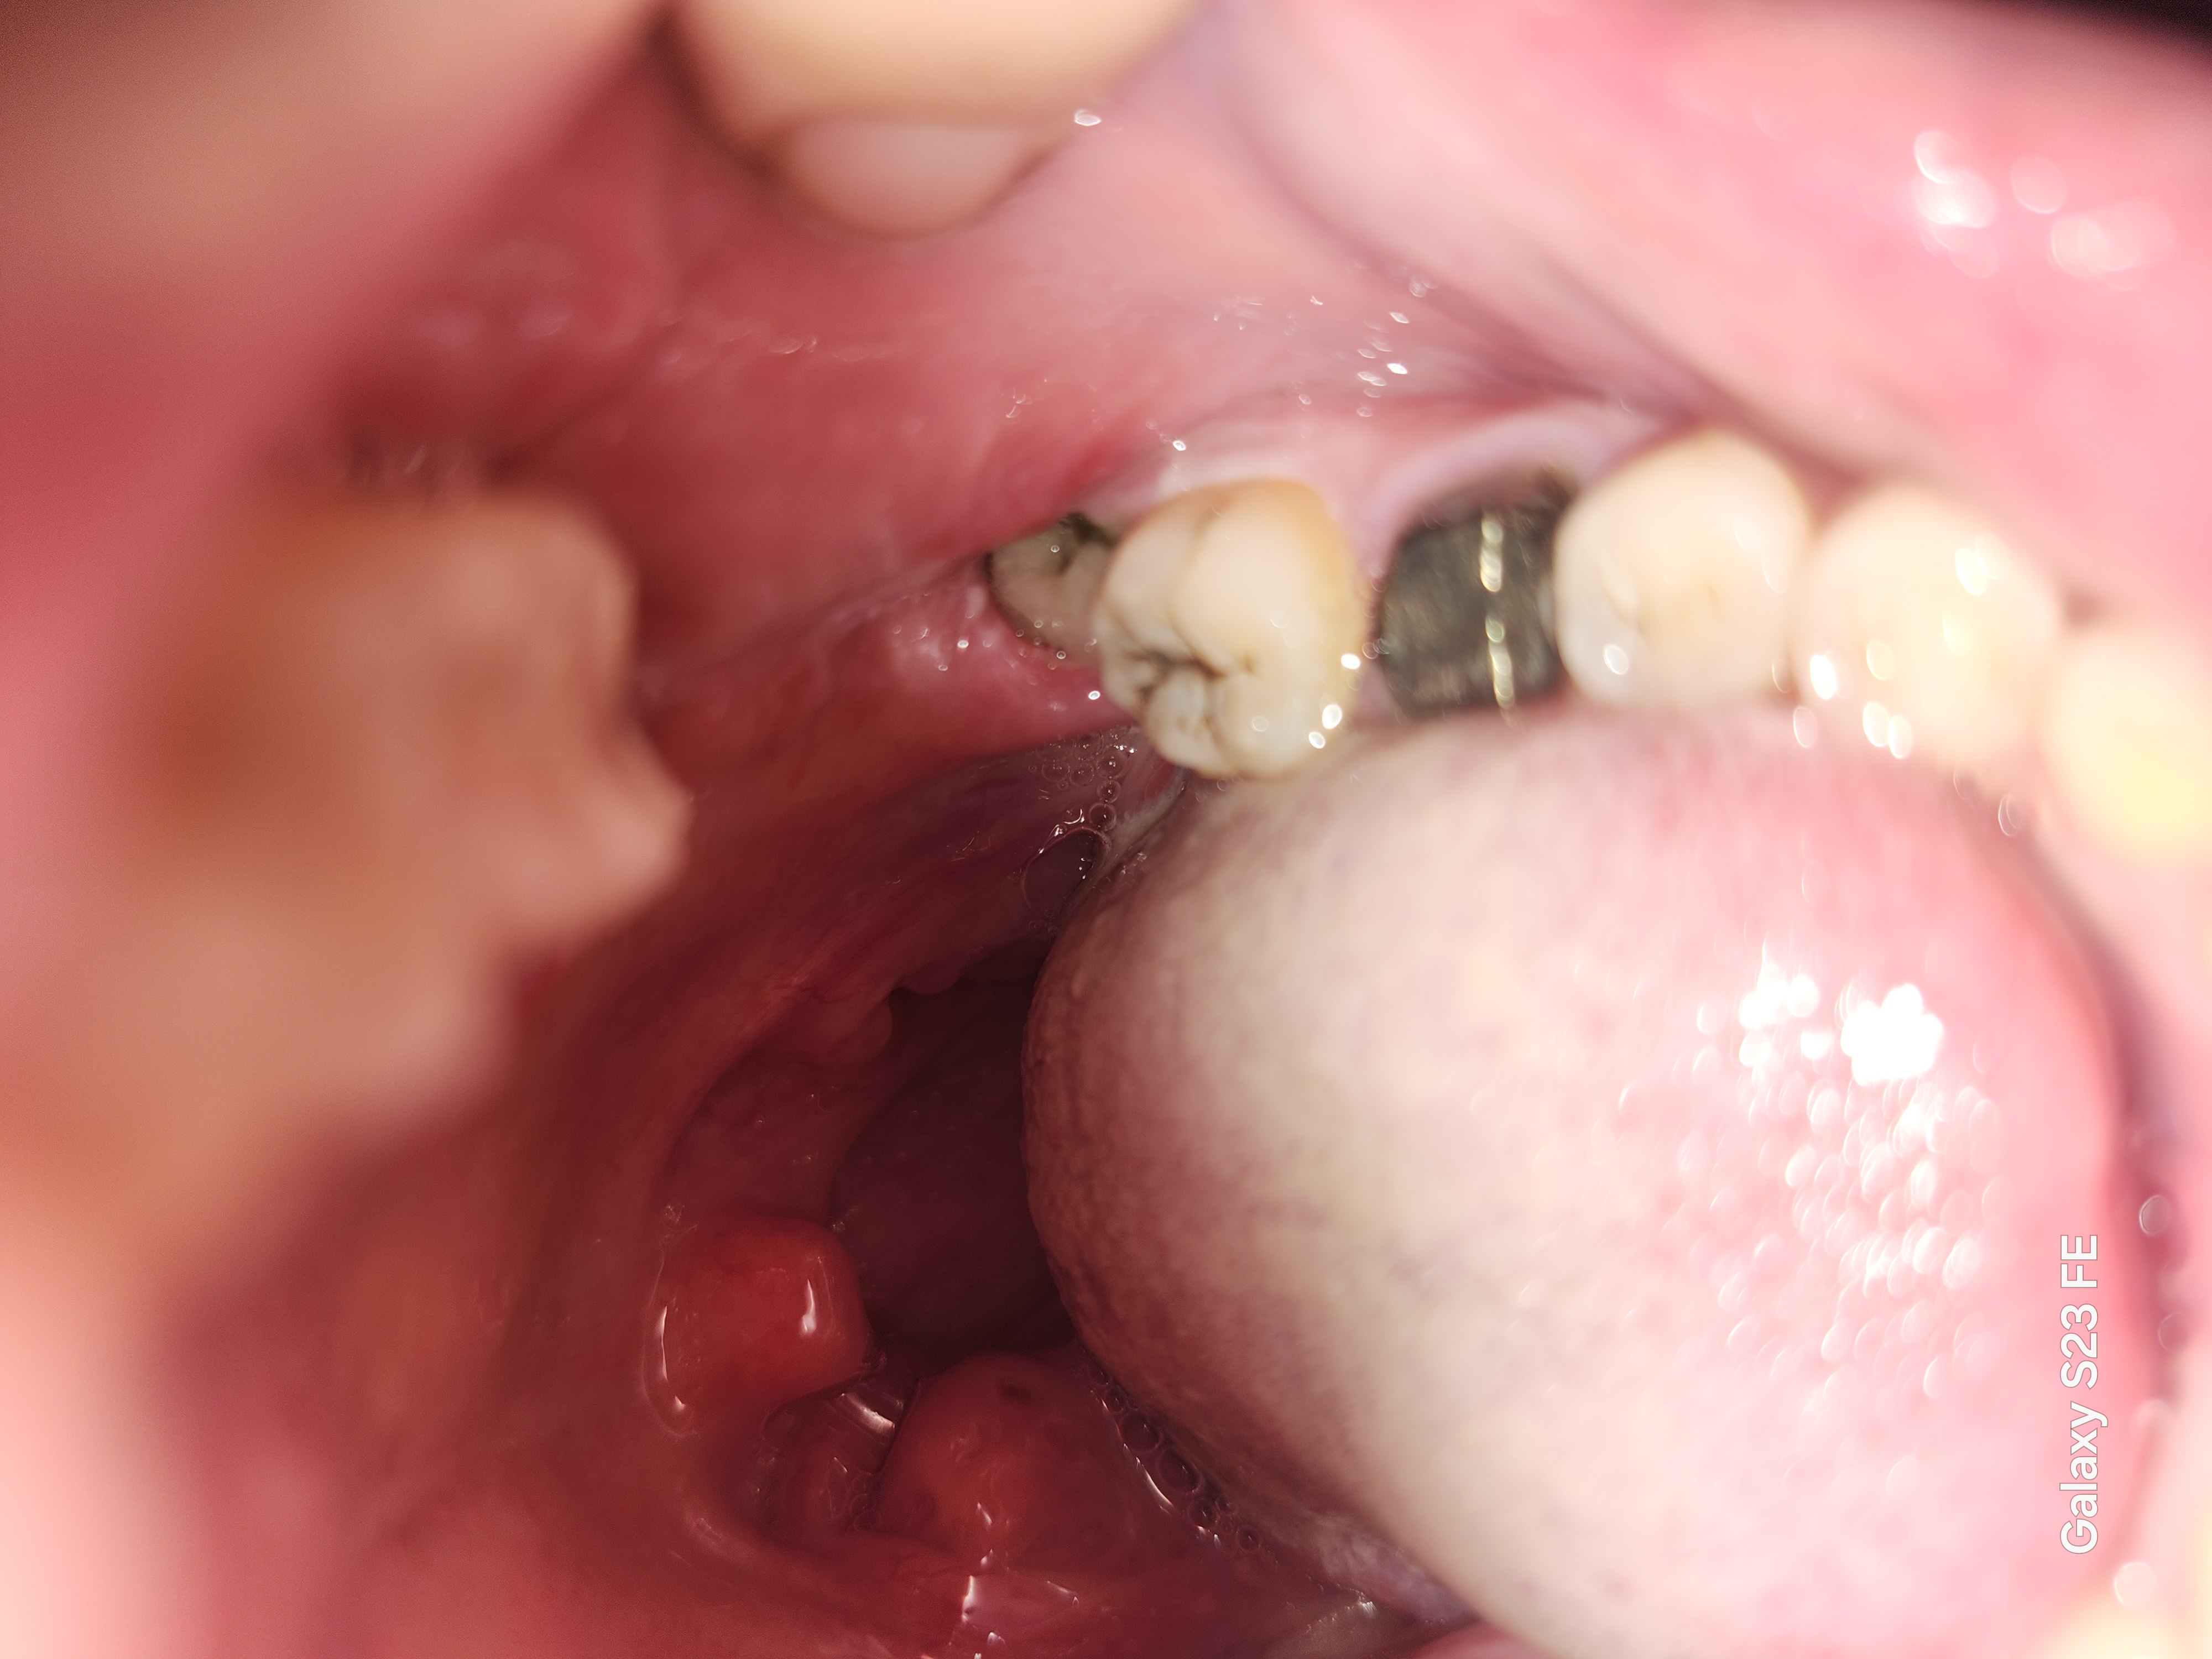

2か月前に親知らずを抜歯したところの歯茎が腫れて膿のようなものが出ました。